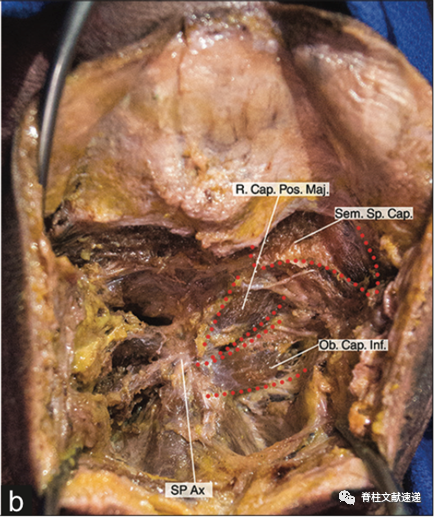

摆好体位后,透视确认寰枢椎,后正中切开。要确保沿中线切开以减少出血,自动拉勾撑开浅层,可识别出后方肌群。注意保护尾端的颈半棘肌。(Sp.Cap:头夹肌,Trap:斜方肌,R.Cap.Pos.Maj:头后大直肌,SemispinalisCapitismuscle:头半棘肌,Ob.Cap.Inf:头下斜肌,SPAx:枢椎棘突)。